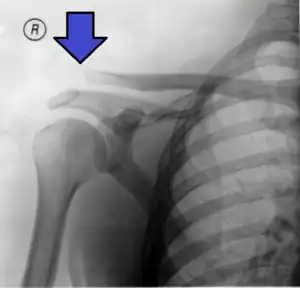

| An Xray showing a separated shoulder. Notice the separation between the end of the collarbone and the scapula. | |

X-ray indicates a separated shoulder when the acromioclavicular joint space is widened (it is normally 5 to 8 mm),[11]it can be classified into 6 types.